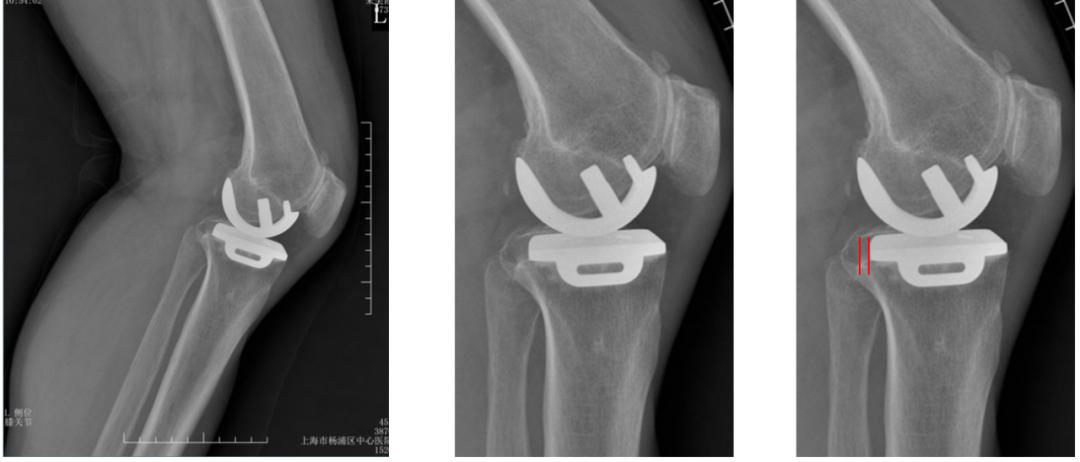

五、辨别生理性透亮线

透亮线形成过程

透亮线的意义

生理性透亮线的定义:

宽度≤2mm、边界清晰锐利、非进行性增宽,常伴平行致密硬化线。在术后头两年形成,随后保持稳定。不提示假体松动、感染或失败。